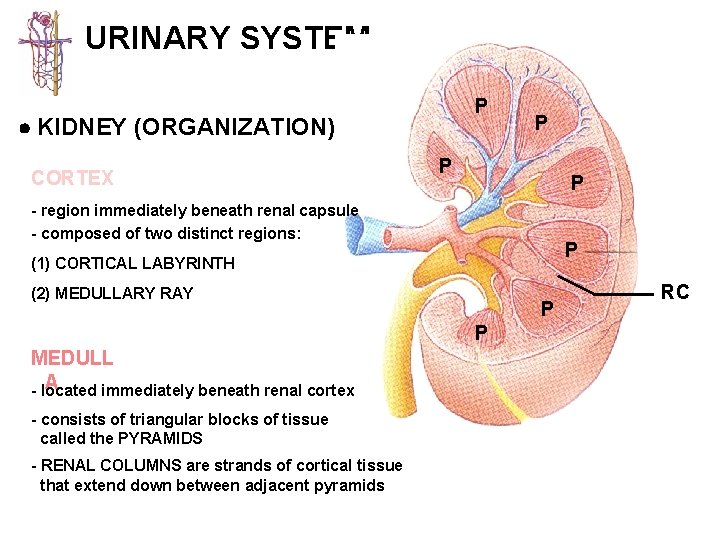

URINARY SYSTEM P KIDNEY (ORGANIZATION) CORTEX P P P - region immediately beneath renal capsule - composed of two distinct regions: P (1) CORTICAL LABYRINTH (2) MEDULLARY RAY P P MEDULL A - located immediately beneath renal cortex - consists of triangular blocks of tissue called the PYRAMIDS - RENAL COLUMNS are strands of cortical tissue that extend down between adjacent pyramids RC